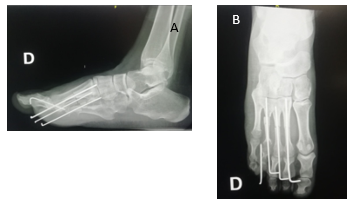

En la radiología se observa un cuarto metatarsiano hipoplásico bilateral, sin afectación de las falanges. Este es curvo, no presenta subluxación de la articulación metatarsofalángica. Dicha articulación no ofrece alteraciones degenerativas artrósicas. Se constata la interrupción de la parábola metatarsal (Figura 2) Según la clasificación radiográfica de Lamm es 4A. 3

Figura 2: Radiografía de frente. Se constata la alteración de la parábola metatarsal mayor en el pie izquierdo. Un cuarto metatarsiano corto, subluxación de la articulación metatarso falángica.

Comienza apoyo parcial progresivo a los 2 meses reintegrándose a sus tareas habituales a los 6 meses. La consolidación ósea se obtuvo a los 2 meses. (Figura 4)

Figura 3: A: Abordaje dorsal centrado en el 4o. metatarsiano. Liberación de los músculos interóseos. A: colocación de injerto tricortical de cresta ilíaca. Previo se realizó osteotomía a nivel del osteotomía a nivel del 4o.

Con un seguimiento de 5 años de evolución el paciente está conforme con el resultado estético y funcional, con un Score AOFAS 55/100. Presenta una hiperqueratosis indolora a nivel de la cabeza del quinto metatasiano, un pliegue plantar indoloro y una leve elevación de la articulación metatarso falángica, teniendo congruencia articular. No la limita en sus actividades diarias. (Figura 5 y 6)

Se logra un alargamiento de 1.2 mm que en la evolución presenta una reabsorción del injerto y leve pérdida de la reducción de éste, teniendo un alargamiento de 0.9 mm a los 5 años.